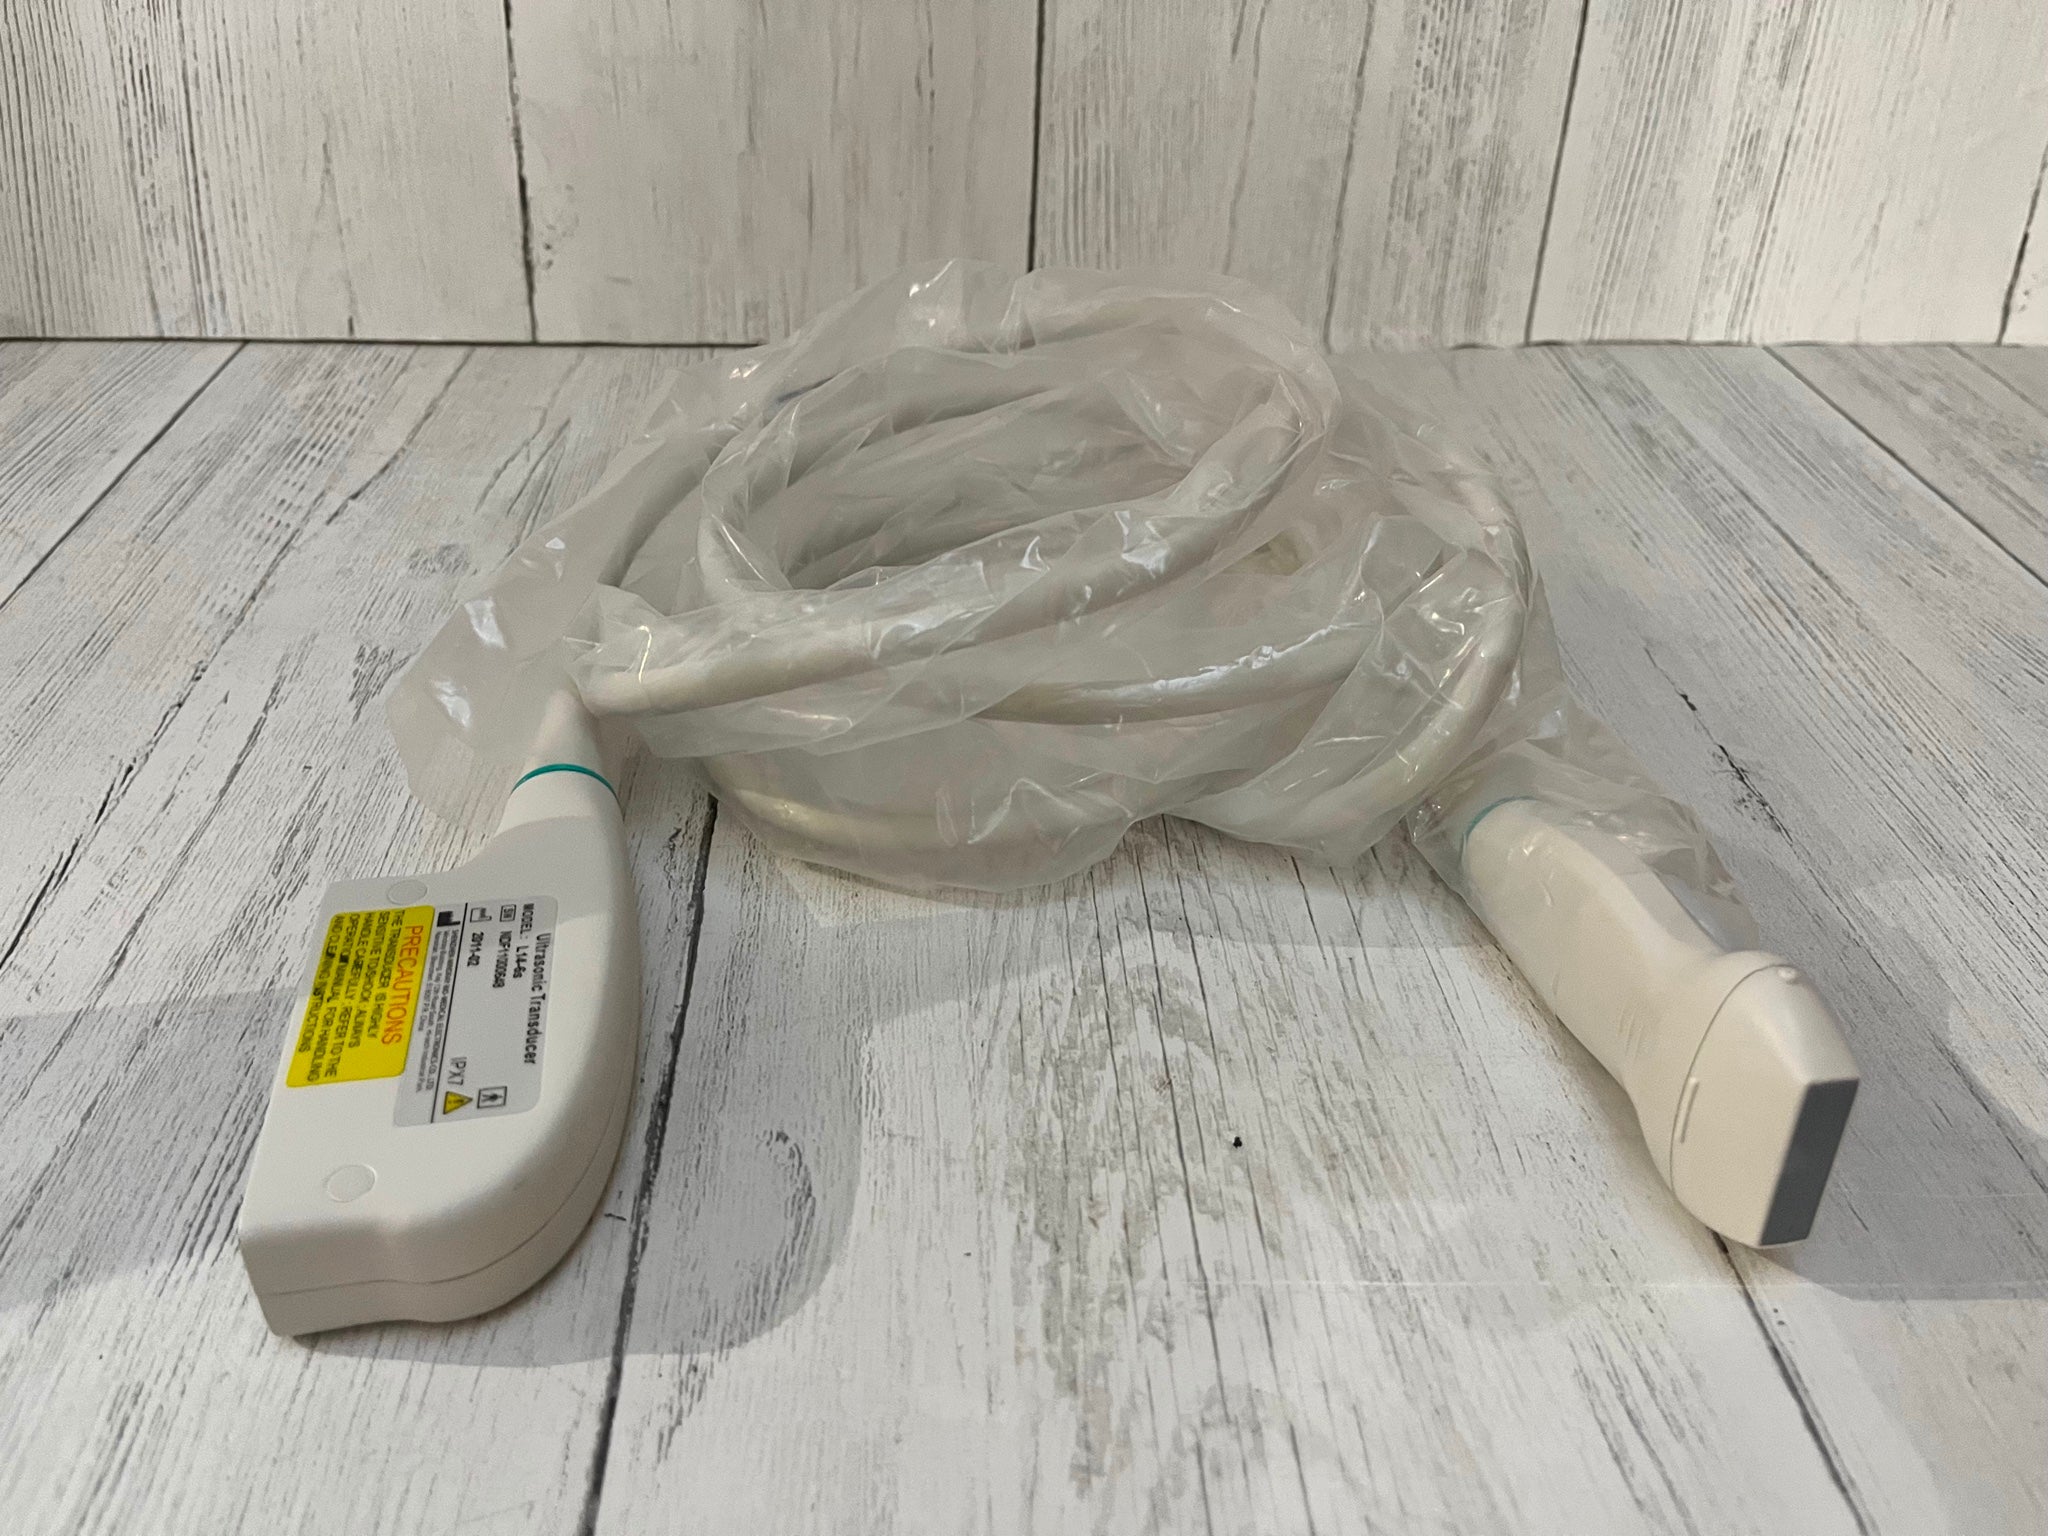

Condition: Used: An item that has been used previously. The item may have some signs of cosmetic wear, but is fully operational and functions as intended. This item may be a floor model or store return that has been used. See the sellerâs listing for full details and description of any imperfections. See all condition definitions- opens in a new window or tab ... Read moreabout the condition

The Ultrasound probe SIEMENS Acuson 4C1 employs cutting-edge imaging technology to provide high-resolution images that enhance diagnostic capabilities. It uses a linear array transducer, which allows it to capture detailed anatomical structures in real-time. This technology improves the clarity of the images, making it easier for healthcare professionals to identify and assess various conditions. Because of its advanced features, this probe is indispensable in ultrasound examinations.

The SIEMENS Acuson 4C1 is designed with ease of use in mind. It features an ergonomic design that allows for comfortable handling during procedures. Additionally, the probe connects seamlessly to SIEMENS ultrasound systems, ensuring smooth operation. This compatibility streamlines workflow in a clinical setting, as healthcare providers can easily transition between different imaging tasks. Therefore, its user-friendly nature contributes to efficiency in the medical workplace.